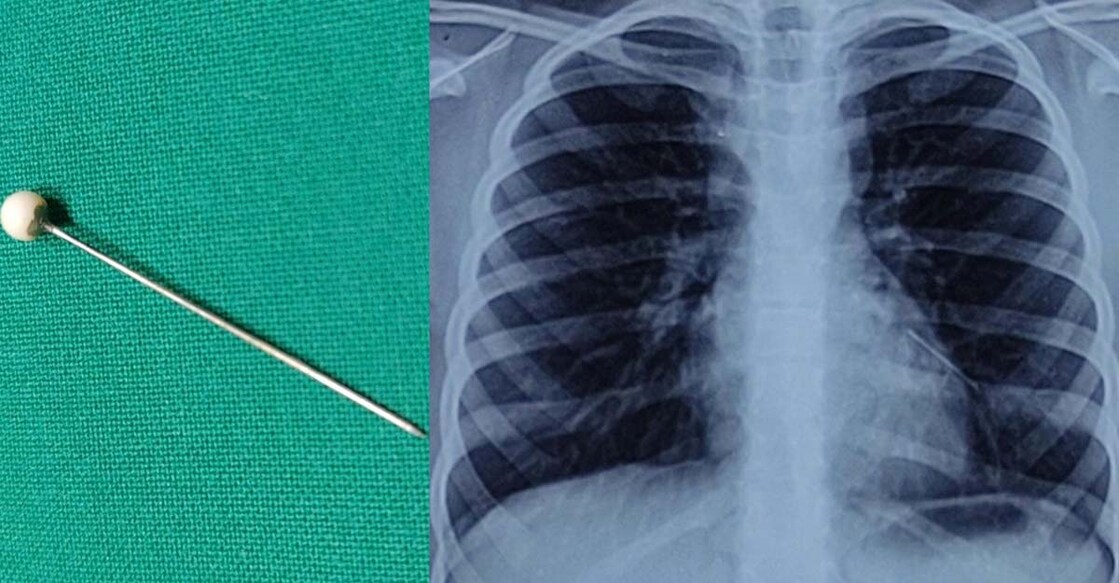

They took her to the Zen Multispeciality Hospital here which conducted an x-ray on the girl's chest to make a shocking discovery.

"To our utter surprise, the chest x-ray revealed a metallic foreign body in the lower airway (the breathing tube) on the left side. A CT-scan was performed to determine the precise location of the foreign object," said ENT Surgeon Dr. Kshitij Shah.

"The foreign body was successfully removed without any complications or leaving any external scars on her body. She recovered quickly and was discharged after two days," Dr. Shah said.